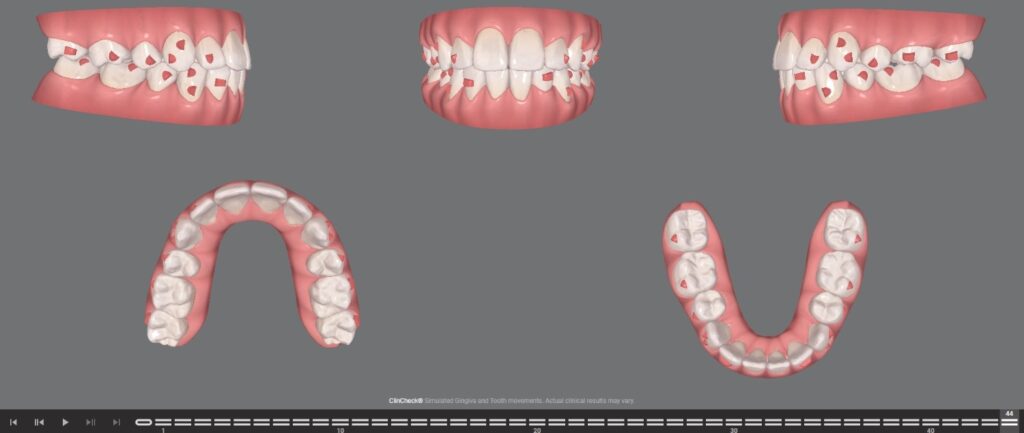

PLANNED SETUP-

Stage-by-Stage Treatment Progress

After scanning & record documentation-A 3D model is generated. After that,The 3D ClinCheck software shows how your teeth will move after extraction. The aligners close the extraction gaps gradually with controlled force. The teeth will move sequentially with each tray. Each tray shifts the teeth about 0.25 mm. Smart Force attachments and elastics help in canine retraction with Invisalign, pulling teeth gently into place. In Cases for larger movements, orthodontists may use TAD-They are small anchor screws that give better control. This helps in proper incisor retraction with aligners without losing anchorage.

- After four premolar extractions, the G6 protocol was utilized in Clinic Check for anterior retraction and space closure i.e. maximum anchorage

- G6 attachments and staging were used to retract the anterior teeth.

- Optimized Maximum Anchorage Attachments for first premolar extraction were incorporated into the plan. SmartForce aligner activation was used along with these attachments on the posterior teeth to maximize posterior anchorage.

- Optimized Retraction Attachments were used with SmartForce aligner activation to achieve bodily movement during canine retraction without using a Precision Cut in this case.No elastics were used.

- SmartForce aligner activation was applied to the incisors to minimize unwanted tipping and anterior extrusion during anterior retraction in first premolar extraction treatment.

- Staging of anterior and posterior movements was planned to occur simultaneously.

- In all quadrants, only the canines were retracted first-up to one-third of their total movement—and then the incisors were retracted en masse.

- Conventional horizontal attachments were placed on all second molars and lateral incisors, as they did not receive G6 attachments.